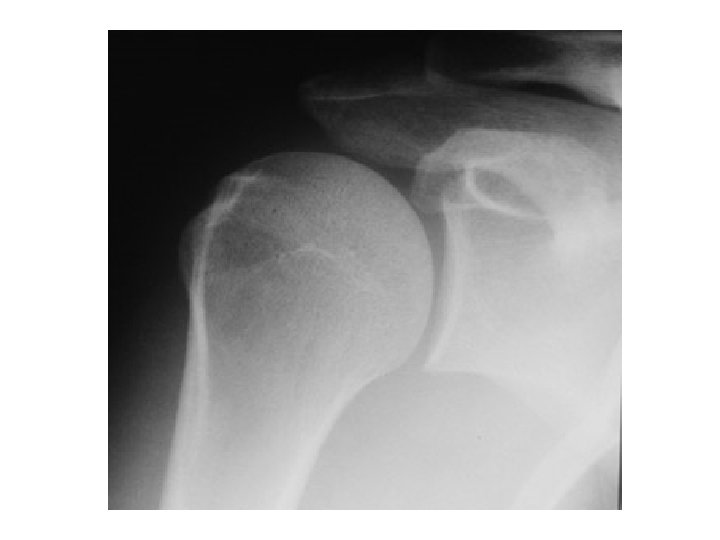

Normal

Diagnostic Strategies • 1 - True AP